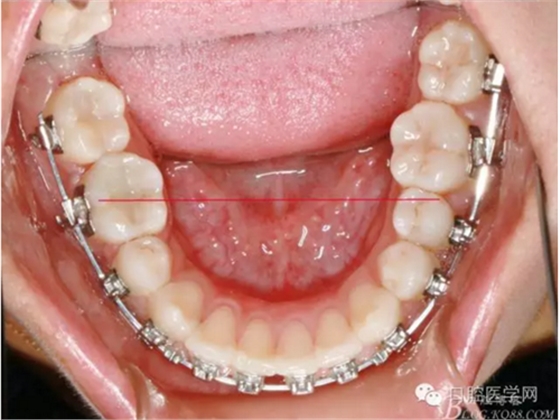

37,45缺失后,鄰牙近中移動(dòng)占據(jù)了部分牙位;患者要求減少治療費(fèi)用,不做種植修復(fù),那怎么協(xié)調(diào)右側(cè)的咬合關(guān)系?

15是根管治療過的牙齒,只好忍痛舍去......

在滿足功能的前提下,退而求其次...有時(shí)候,正畸醫(yī)生不得不妥協(xié)。